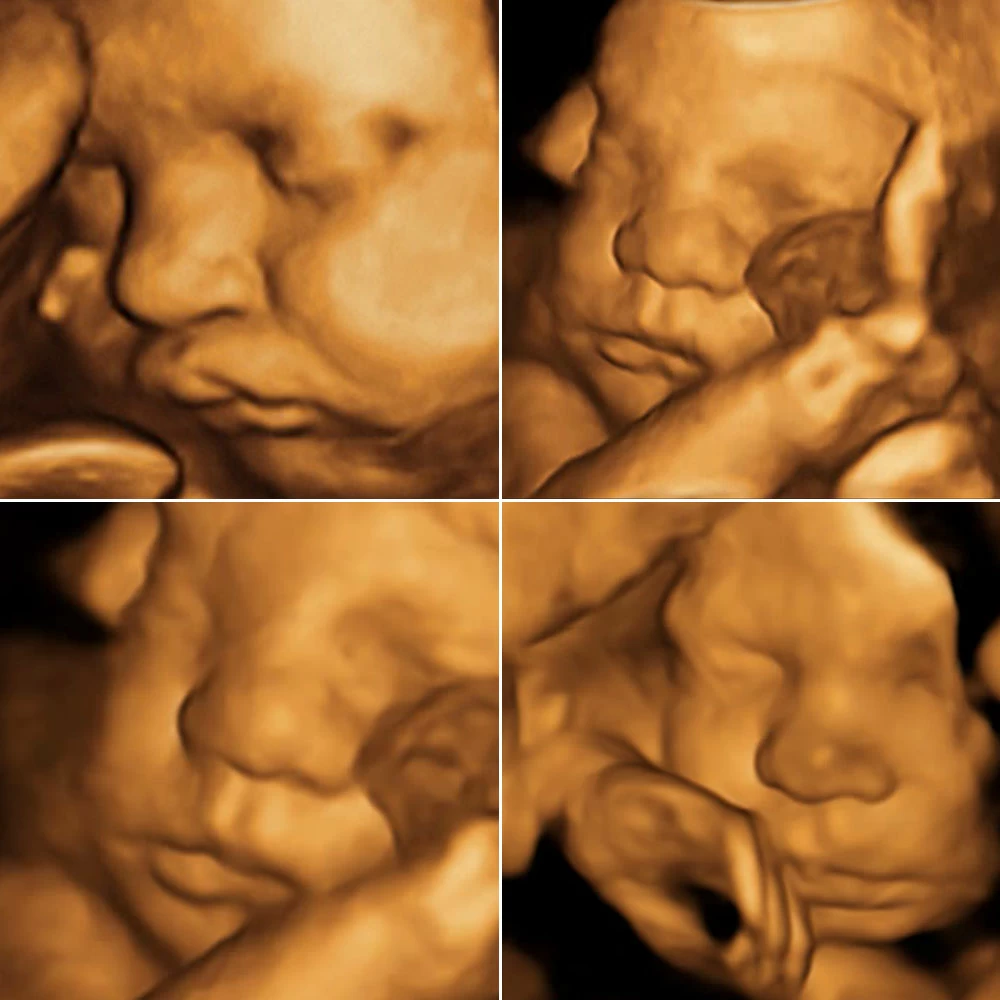

На 22 неделе размеры плода увеличиваются до 28 см, вес – до 450-500 грамм. Размеры головки становятся пропорциональны туловищу и конечностям. Ноги практически все время находятся в согнутом состоянии.

Совершенствуется нервная система плода: головной мозг содержит уже все нервные клетки (нейроны) и имеет массу около 100 грамм. Ребенок начинает интересоваться своим телом: ощупывает свое лицо, руки, ноги, наклоняет голову, подносит пальцы ко рту.

Длина тела плода составляет 28-30 см, масса – около 500 грамм. В коже начинает синтезироваться пигмент, в результате кожа приобретает ярко-красный цвет. Подкожная жировая клетчатка еще достаточно тонкая, в результате ребенок выглядит очень худым и сморщенным.

К концу этой недели масса плода увеличивается до 600 грамм, длина тела – до 30-32 см.

Лицо имеет привычный для человека вид.